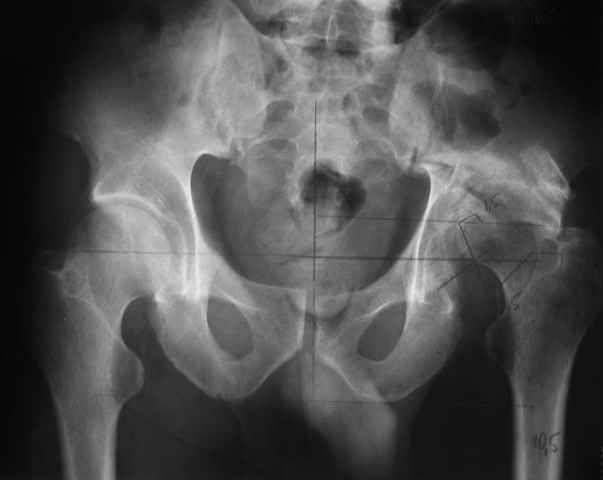

Our experience showes, that reposition and stabilization pelvis in zone of old acetabular fractures with bone grafting are very traumatic and not effective due head AVN and hip arthrosis.

In such cases we use hip arthroplasty with "Octopus" acetabular system (De Puy). This system consist of acetabular ring and cementless cup.

It`s allow you to fix the reinforcement ring in proper position, then bone grafting of the defects of the acetabulum walls and floor.

Then you fix the cup to the ring.

I will show some cases.